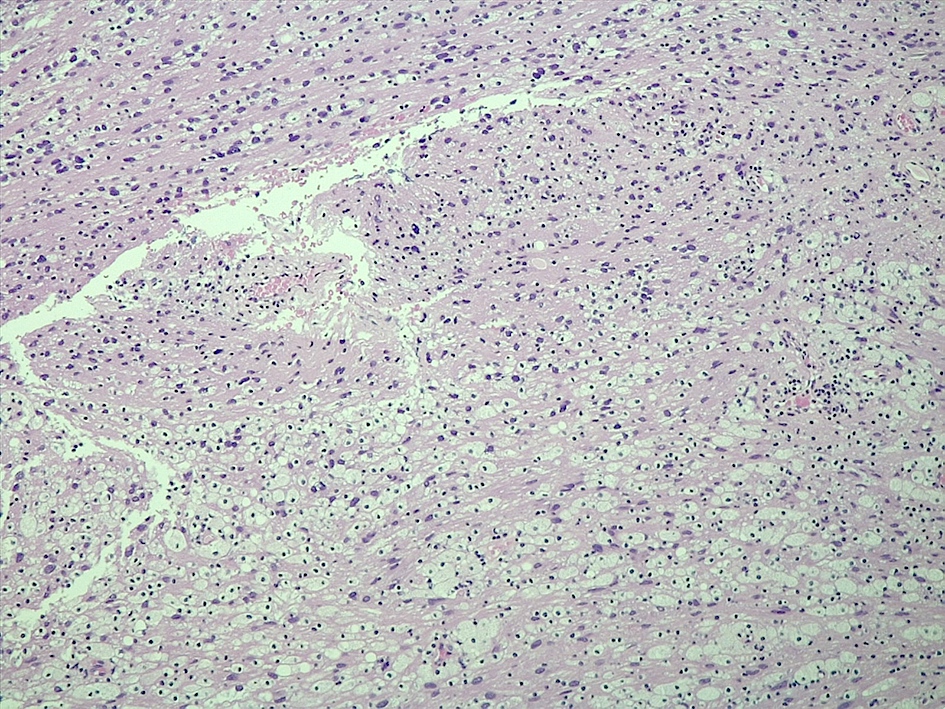

Microscopic (histologic) description

- Spindle cell tumor (usually biphasic) and composed of compact hypercellular areas (Antoni A tissue) showing nuclear palisading (Verocay bodies) and loose microcystic areas (Antoni B tissue) with collection of lipid laden histiocytes and thick walled hyalinized blood vessels (Surg Neurol Int 2020;11:454)

- Lymphoid aggregates maybe seen peripherally or in a subcapsular distribution

Microscopic (histologic) images